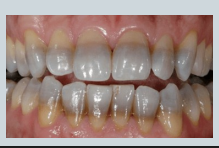

abnormal colour of teeth - what causes banding?

tetracycline (antibiotic) during odontogenesis (pregnancy/ very young children)

abnormal colour of teeth - what causes mottling?

fluorosis - excess fluoride

abnormal colour of teeth - what causes olive green teeth?

childhood jaundice/liver disfunction - through its very rare

abnormal colour of teeth - what causes purple/red teeth?

prophyria - rare inherited condition where you get porphyrin build up in the body - translucent looking red/purple teeth

porphyrin is needed to make red blood cells - build up in the body

abnormal colour of teeth - what causes translucent brown/purple teeth ?

dentinogenesis imperfecta

blue sclera and brittle bones